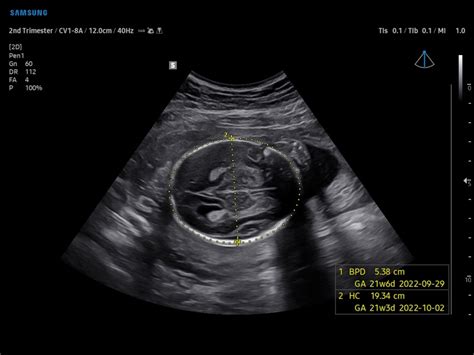

IBPd: Interpreting the Biparietal Diameter

Alright, let’s get into the first acronym: IBPd . This stands for Biparietal Diameter , which is the measurement of the baby’s head. Specifically, it refers to the diameter of the head from one parietal bone to the other. Think of it like measuring the widest part of the baby’s head. The IBPd measurement is one of the key indicators used to estimate your baby’s gestational age and to assess head growth. This measurement helps determine if the baby’s head size is appropriate for its age. The IBPd is typically measured in millimeters, and the values are compared against a standard growth chart that shows the expected range for each week of pregnancy. Deviations from the expected range can sometimes indicate potential issues, such as macrosomia (a larger-than-average baby) or microcephaly (a smaller-than-average head). However, it is important to remember that a single measurement alone doesn’t tell the whole story. Your doctor will consider the IBPd in conjunction with other measurements and assessments.

HC: Deciphering Head Circumference

Next up, we have HC , which stands for Head Circumference . The HC measurement is the circumference of the baby’s head, which gives a comprehensive assessment of the head’s size. Like the IBPd, the HC is a critical parameter for monitoring fetal development. By measuring the HC, your doctor can gain more insight into the baby’s growth trajectory and identify any potential developmental issues. The HC measurement complements the IBPd, providing a more complete picture of the head’s dimensions and growth rate. This holistic approach helps to get a more accurate assessment of the baby’s well-being. So, let’s dig a bit deeper into what HC is all about.